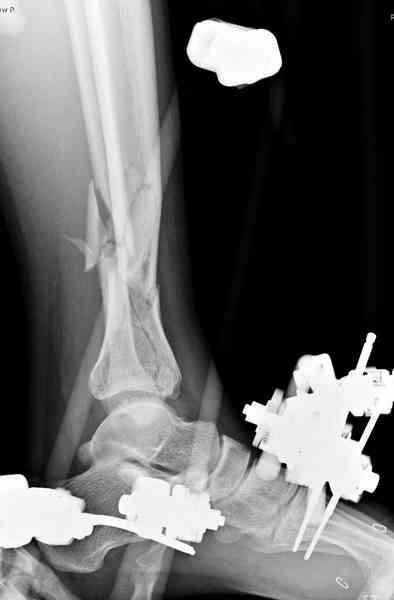

На голень наружный фиксатор, рану на бедре ушили (рана была изнутри кнаружи всего 2 см). По протоколу травматических больных, до операции обследован ангиографически, (у больного дистально не смогли определить пульсацию) сосудистый хирург подтвердил проходимость на всем протяжении магистрального сосуда нижней конечности по снимкам ангиограмм.

На следующее утро в 7 часов осмотрен, у больного отсутствовал пульс на a.dorsalis pedis и на a. tibialis posterior, при пассивном движении первого пальца болевой симптом и отсутствовала чувствительность в поространстве между первым и вторыми пальцами.

Сравнительный повторный мониторинг на компартмент синдром, на голени утром давление поднялось до 70 мм, когда послеоперационные были около 30мм.

Срочная фасциотомия на всех 4 компартментах: латерально и медиально,

кстати было достаточно только латеральной фасциотомии, чтобы услышать на допплере пульсацию,

на бедре измерения не подтвердили подозрения на компартмент синдром и рана была закрыта вакуумной губкой (wound VAC).

В настоящее время больной в реанимации по поводу Черепно Мозговой Травмы и состояние улучшается. Запланировал ушивание раны в пятницу, если позволит состояние мягких тканей и при отсутстви отека возможно удастся просунуть перкутанномедиальную пластину.